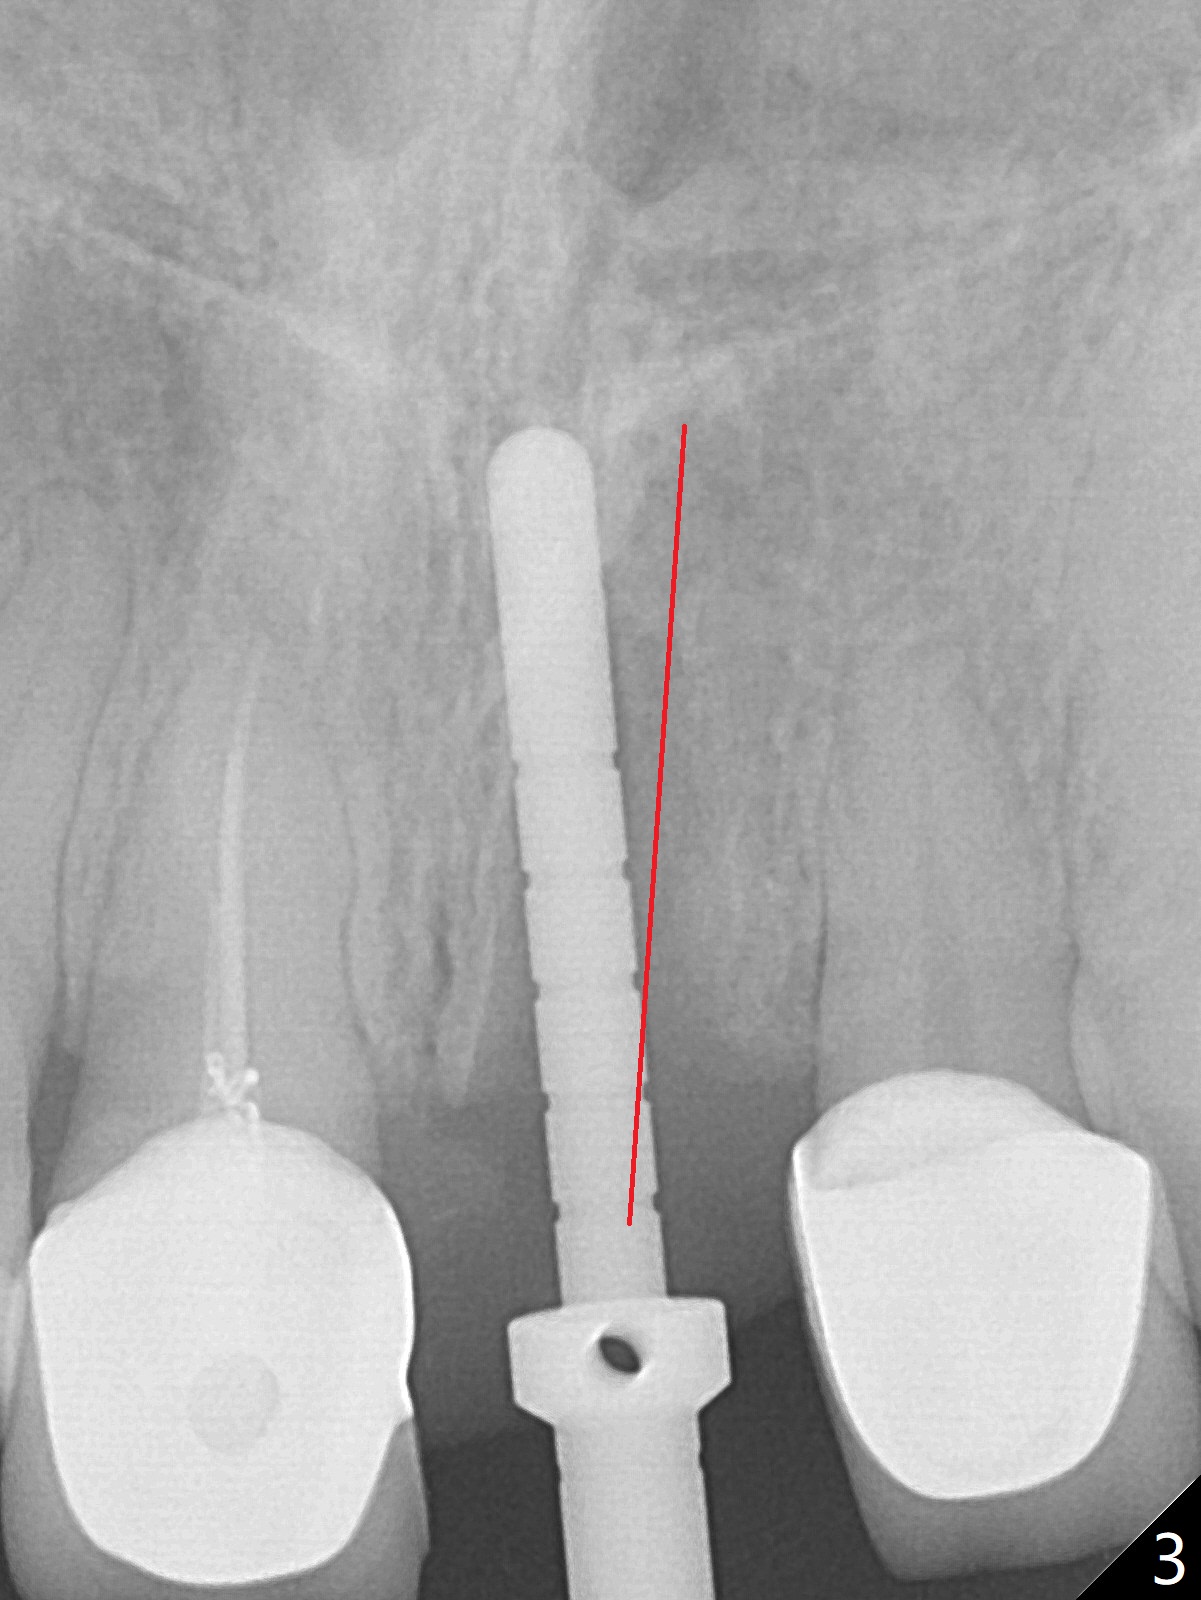

After sectioning the splinted crowns at #8 and 9 (Fig.1,2 (*: open bite)), the tooth #9 is deemed nonsalvageable because of caries and the crown/retainer of #8 is recemented. The trajectory of initial osteotomy is off (Fig.3 (red line: ideal trajectory)). Using Lindamann bur twice does not improve the trajectory (Fig.4,5). It appears that a new osteotomy should be established in the distal wall of the socket (Fig.5 red line (initial entry point and angle), Fig.6). Following sequential osteotomy, a 4x10 mm dummy implant is placed with stability and ~ 3.5 mm apical space (Fig.7 red line). A final implant (4x11.5 mm) is placed subcrestal (except buccal, Fig.8). With further placement of the implant, a 4.5x5.5(3) mm abutment and Vera graft are placed (Fig.9) prior to fabrication of an immediate provisional. In all, a new osteotomy site should be set up when the trajectory is to be changed substantially. There is no gross bone loss 4.5 months postop (Fig.10). There is shade mismatch when a porcelain-fused-Zirconia crown is tried in (Fig.11, as compared to Fig.1). The latter is corrected when a PFM crown is cemented (Fig.12).